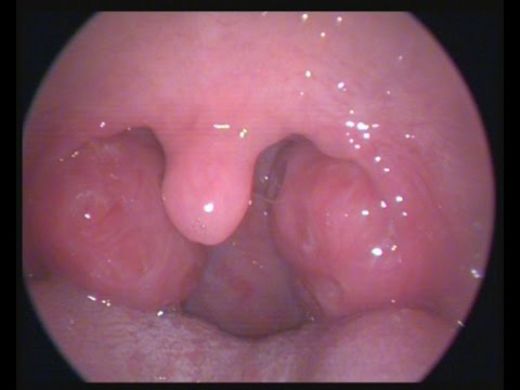

- Cerrahi müdahale: Tekrarlayan bademcik iltihabı durumunda, bademciklerin cerrahi olarak alınması (tonsilektomi) düşünülebilir.

Dikkat Edilmesi Gerekenler

Tek taraflı bademcik şişmesi, bazen daha ciddi durumların bir belirtisi olabileceğinden, doktorun önerilerini dikkatle takip etmekte fayda var. Özellikle ateş, şiddetli ağrı veya nefes alma zorluğu gibi belirtiler varsa, derhal sağlık kuruluşuna başvurmak gerekebilir.